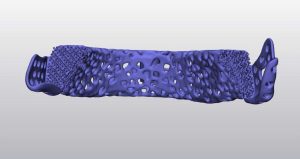

Hình ảnh trên minh họa quá trình thiết kế mô hình implant xương hàm dưới dựa trên dữ liệu CT-Scan. Các bác sĩ và kỹ sư sử dụng phần mềm chuyên dụng để:

Thiết kế implant cá thể hóa: implant được tối ưu về hình dạng, độ dày, và lỗ thoát nhằm tăng cường sự tích hợp sinh học và lưu thông máu.

Nhờ công nghệ in 3D, các mô hình implant được chế tạo với độ chính xác đến từng milimet, hỗ trợ phục hồi chức năng nhai và thẩm mỹ cho bệnh nhân sau phẫu thuật tái tạo xương hàm.